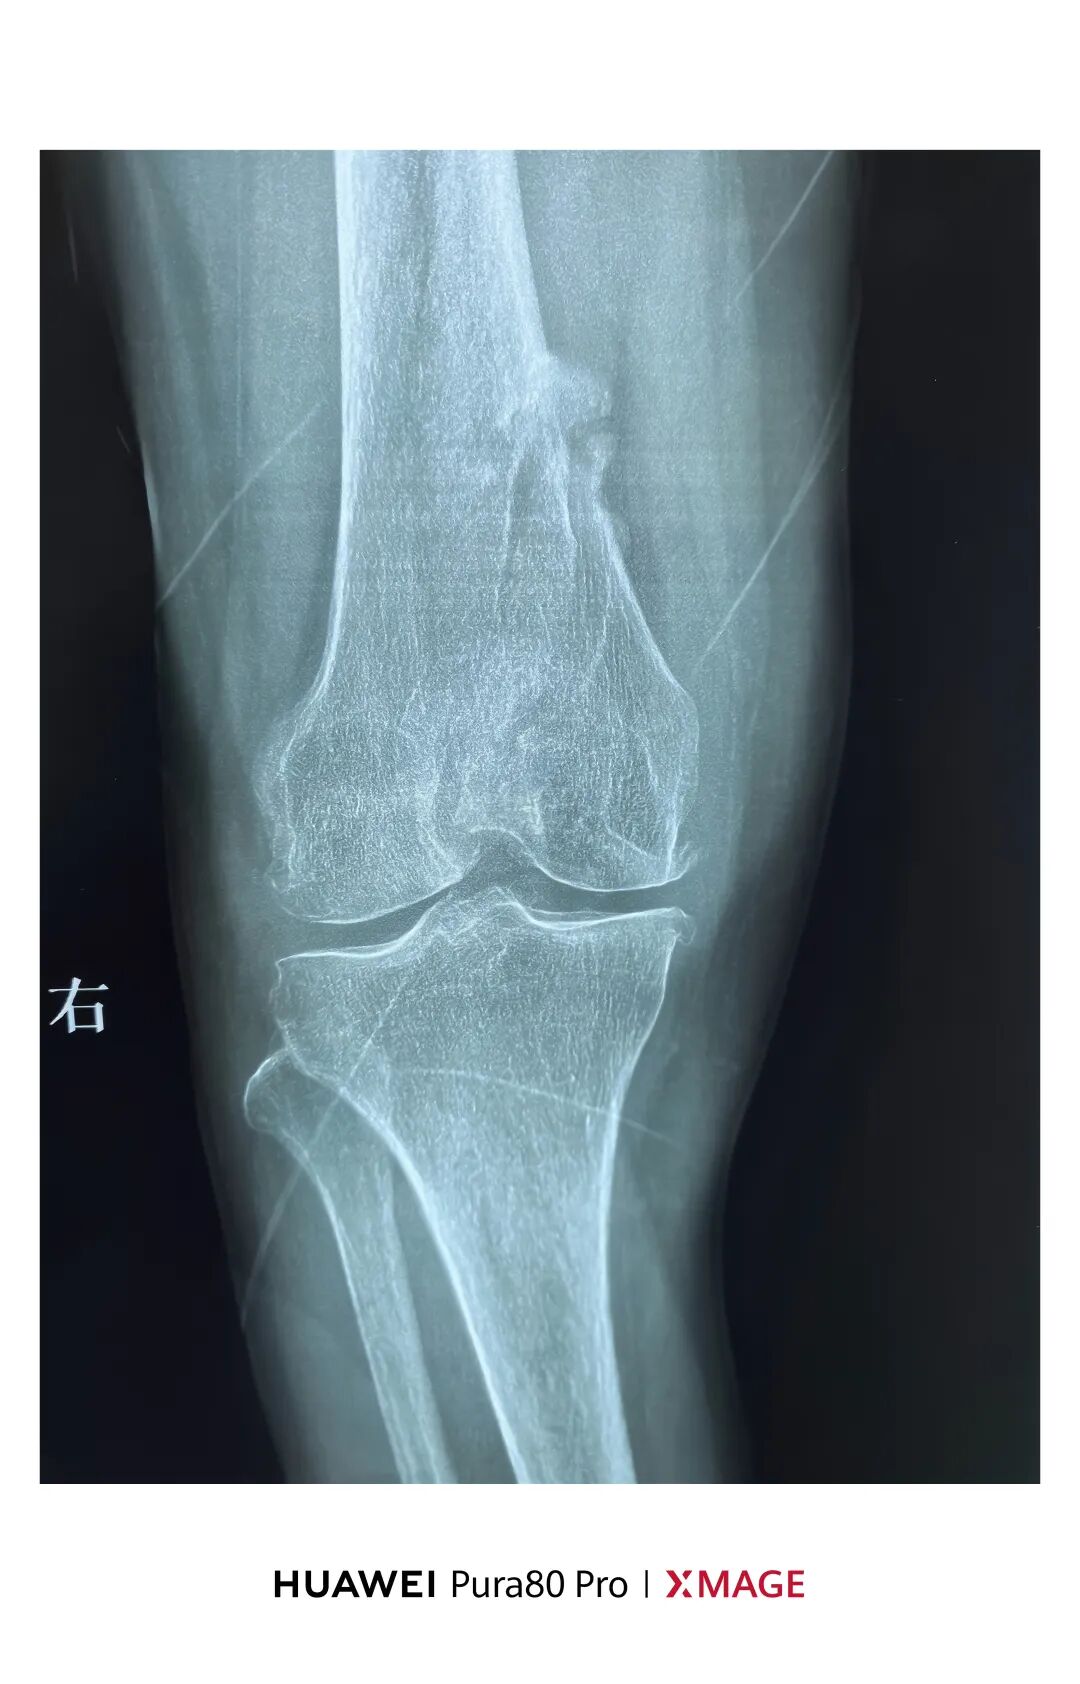

现畸形、疼痛伴活动受限来院

复位满意,力线纠正